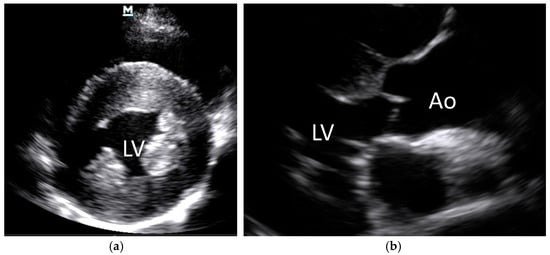

3.2. Systemic Hypertension Lesions

- Nelson, O.L.; Reidesel, E.; Ware, W.A.; Christensen, W.F. Echocardiographic and radiographic changes associated with systemic hypertension in cats. J. Vet. Intern. Med. 2002, 16, 418–425. [Google Scholar] [CrossRef]